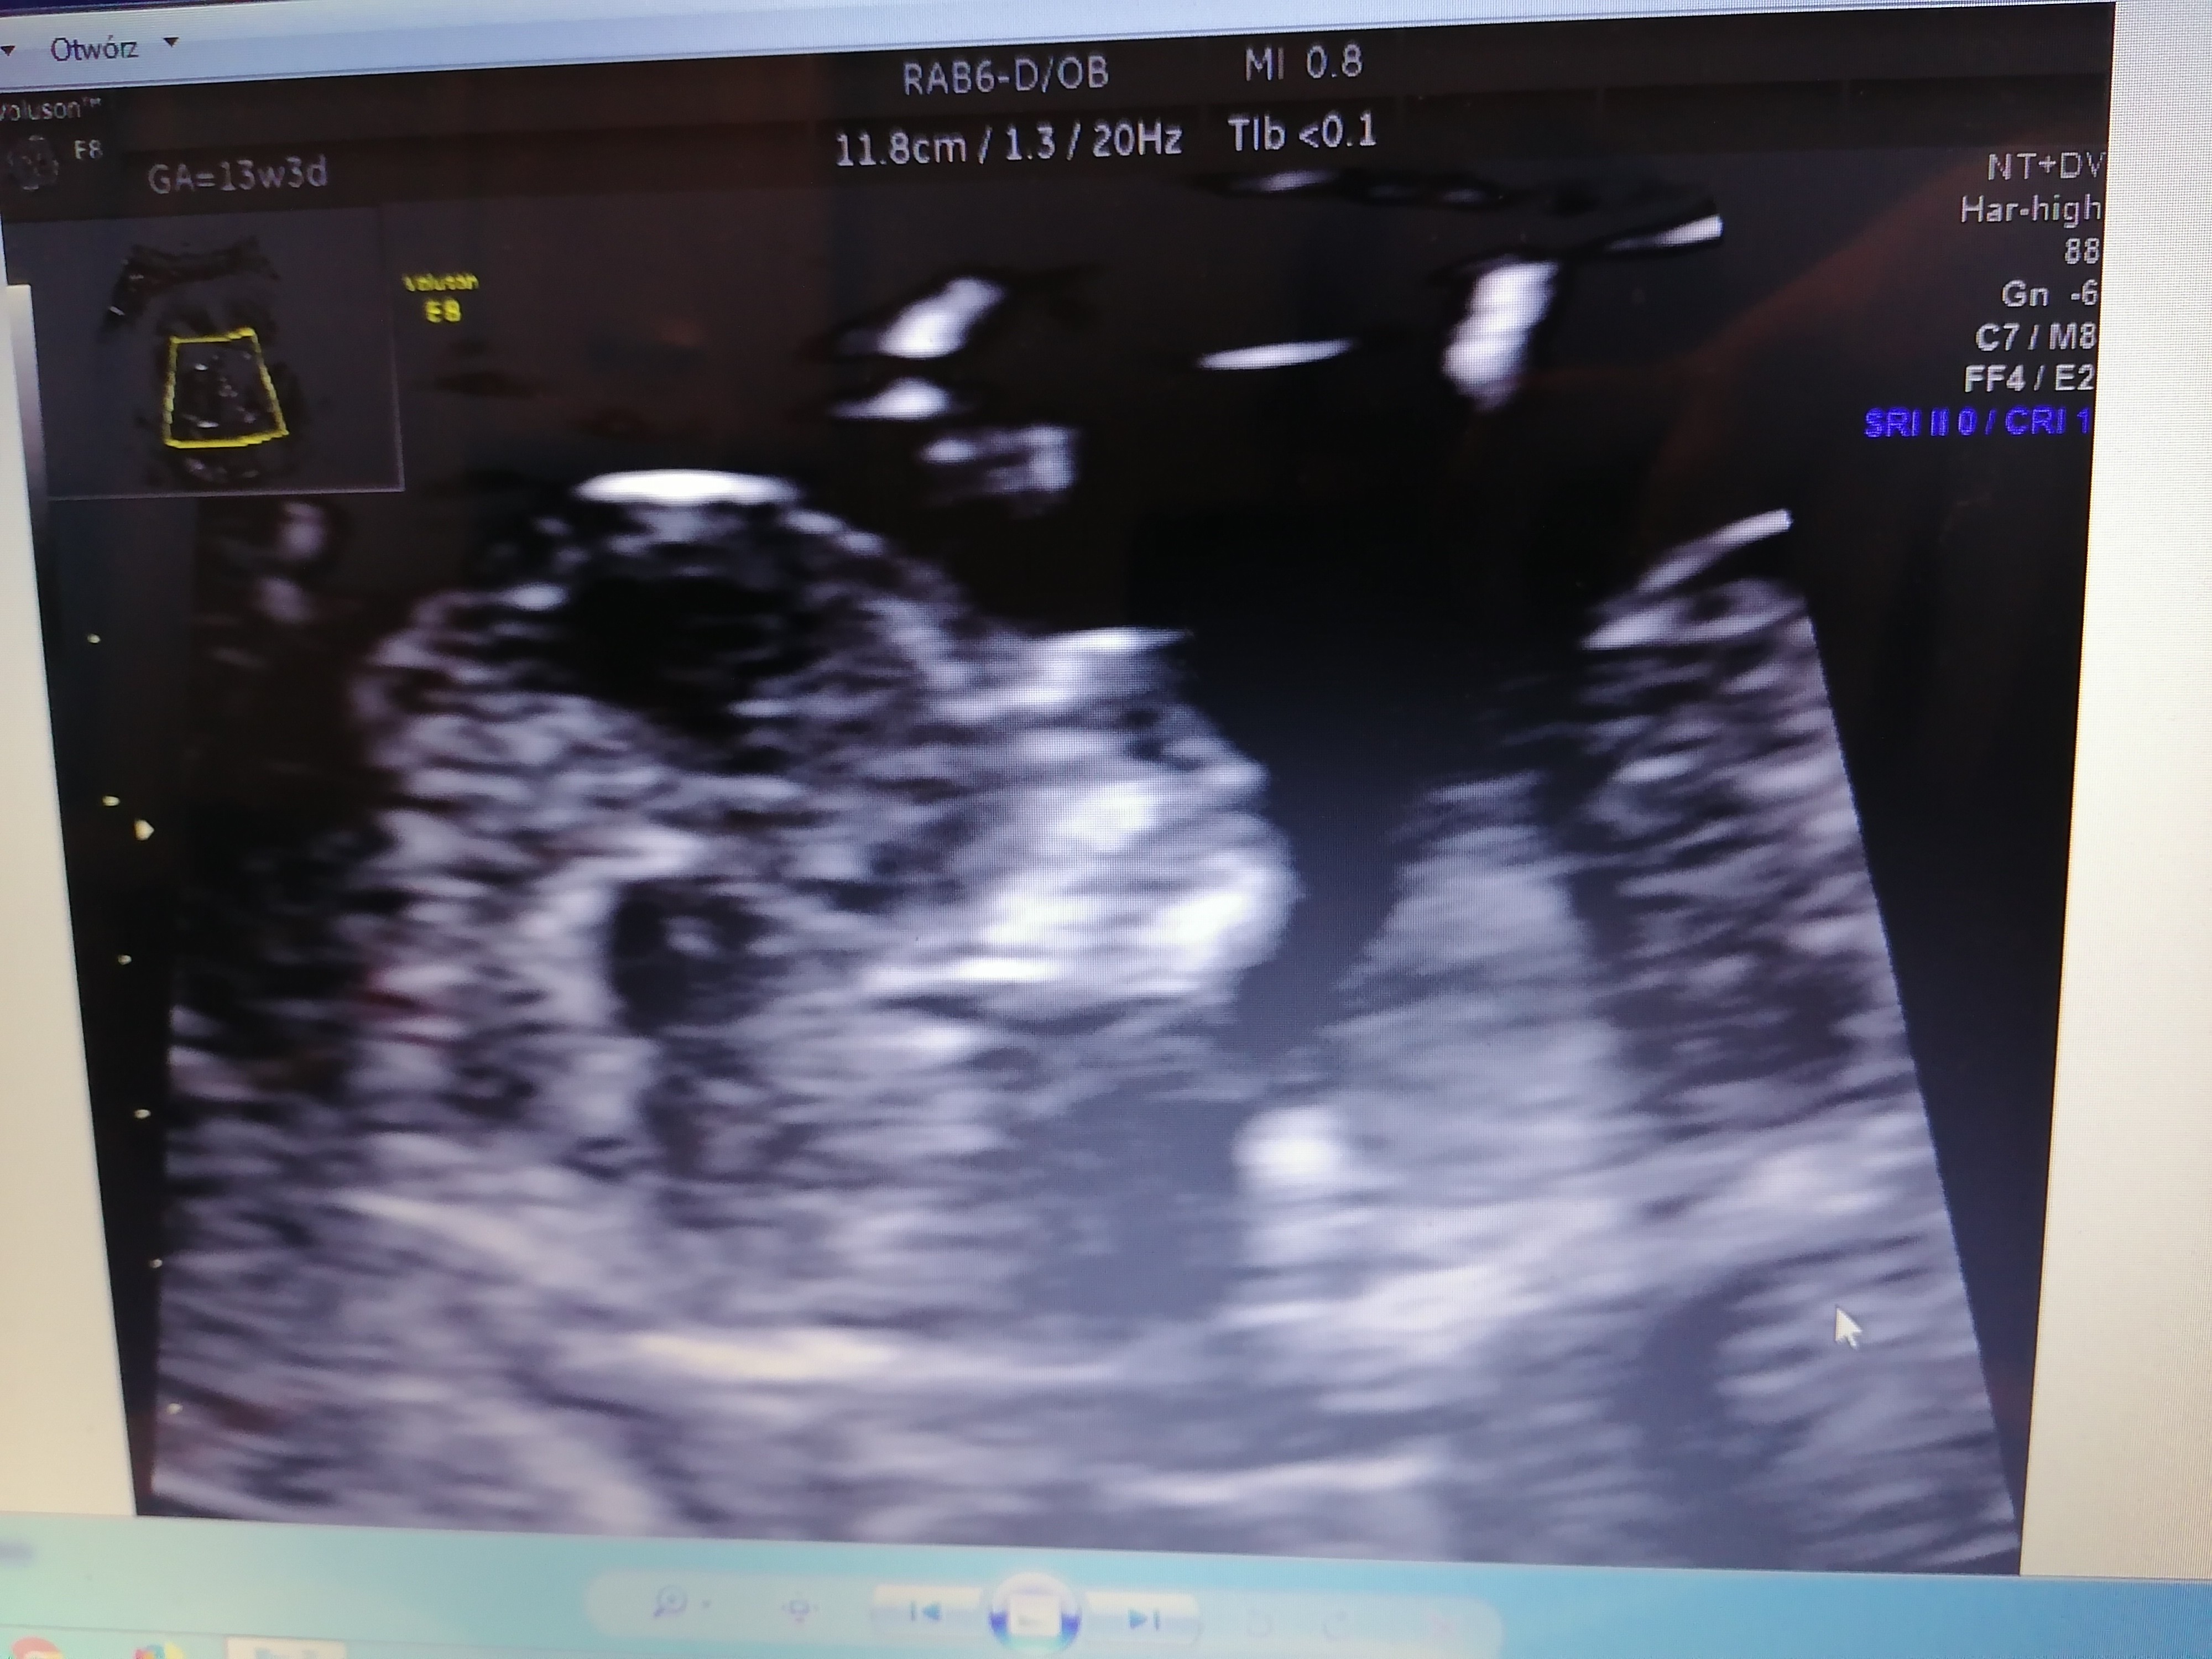

Zrobiłam foto. Mam nadzieję, że już będzie spokojnie do czerwca. Życzę Wam dwóch kreseczek. I jeszcze raz bardzo, bardzo dziękuję za wsparcie. Szczególnie @HeraUnique. Ale i wam wszystkim bardzo mocno ❤️

Jaki już duży dzidzius 😍 Rosnijcie zdrowo i spokojnie do szczęśliwego rozwiązania 👌